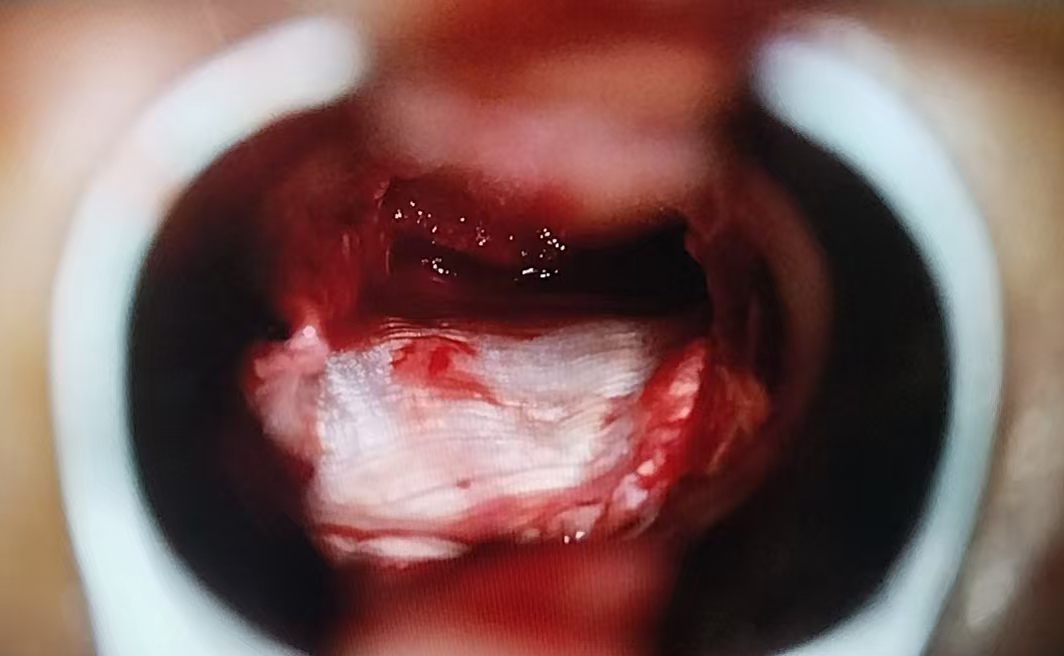

手术当日,在全麻状态下,神经外科团队通过鼻腔这一自然腔道,在神经内镜下清晰暴露术野。精准定位肿瘤位置后,细致操作、逐步切除肿瘤组织,同时妥善修补鞍底硬膜,最大限度保护正常垂体组织,避免损伤周围重要神经与血管。整台手术历时1小时10分钟,术中出血少,无需输血。